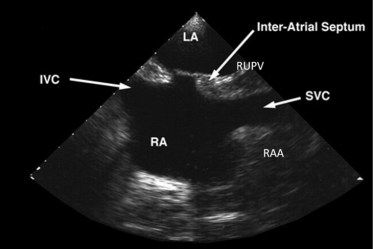

Bicaval view is an Important TEE view to visualize, the LA, IAS, and right atrium. I used to have some trouble getting oriented to this view. Hence this post. It is obtained in the 90-120 degree view at the mid esophageal position. Imagine the patient is lying on his left side and the probe comes from above down between the spine and heart to the LA from within the esophagus. This is the best view to see IAS in the profile.(Subcostal TTE can also do it) Note how the LA hugs the right atrium which is actually an ill-defined (In TEE I mean) common meeting point of both IVC and SVC. Also important is the relationship of RUPV with SVC & the horizontally running RPA sitting right over the top of LA.

The relationship between RUPV and SVC is crucial in device closure of large ASD, especially in sinus venous defect.

Clinical Importance of this view

Very useful in ASD rim morphology especially in the posterosuperior rim.

Delineates clearly the defect boundaries in SVC ASD.

This view doesn’t miss even the smallest PFO (With Contrast )

Can be used to guide IAS puncture in structural heart Interventions.

IVC /SVC mass extension into RA well visualized.